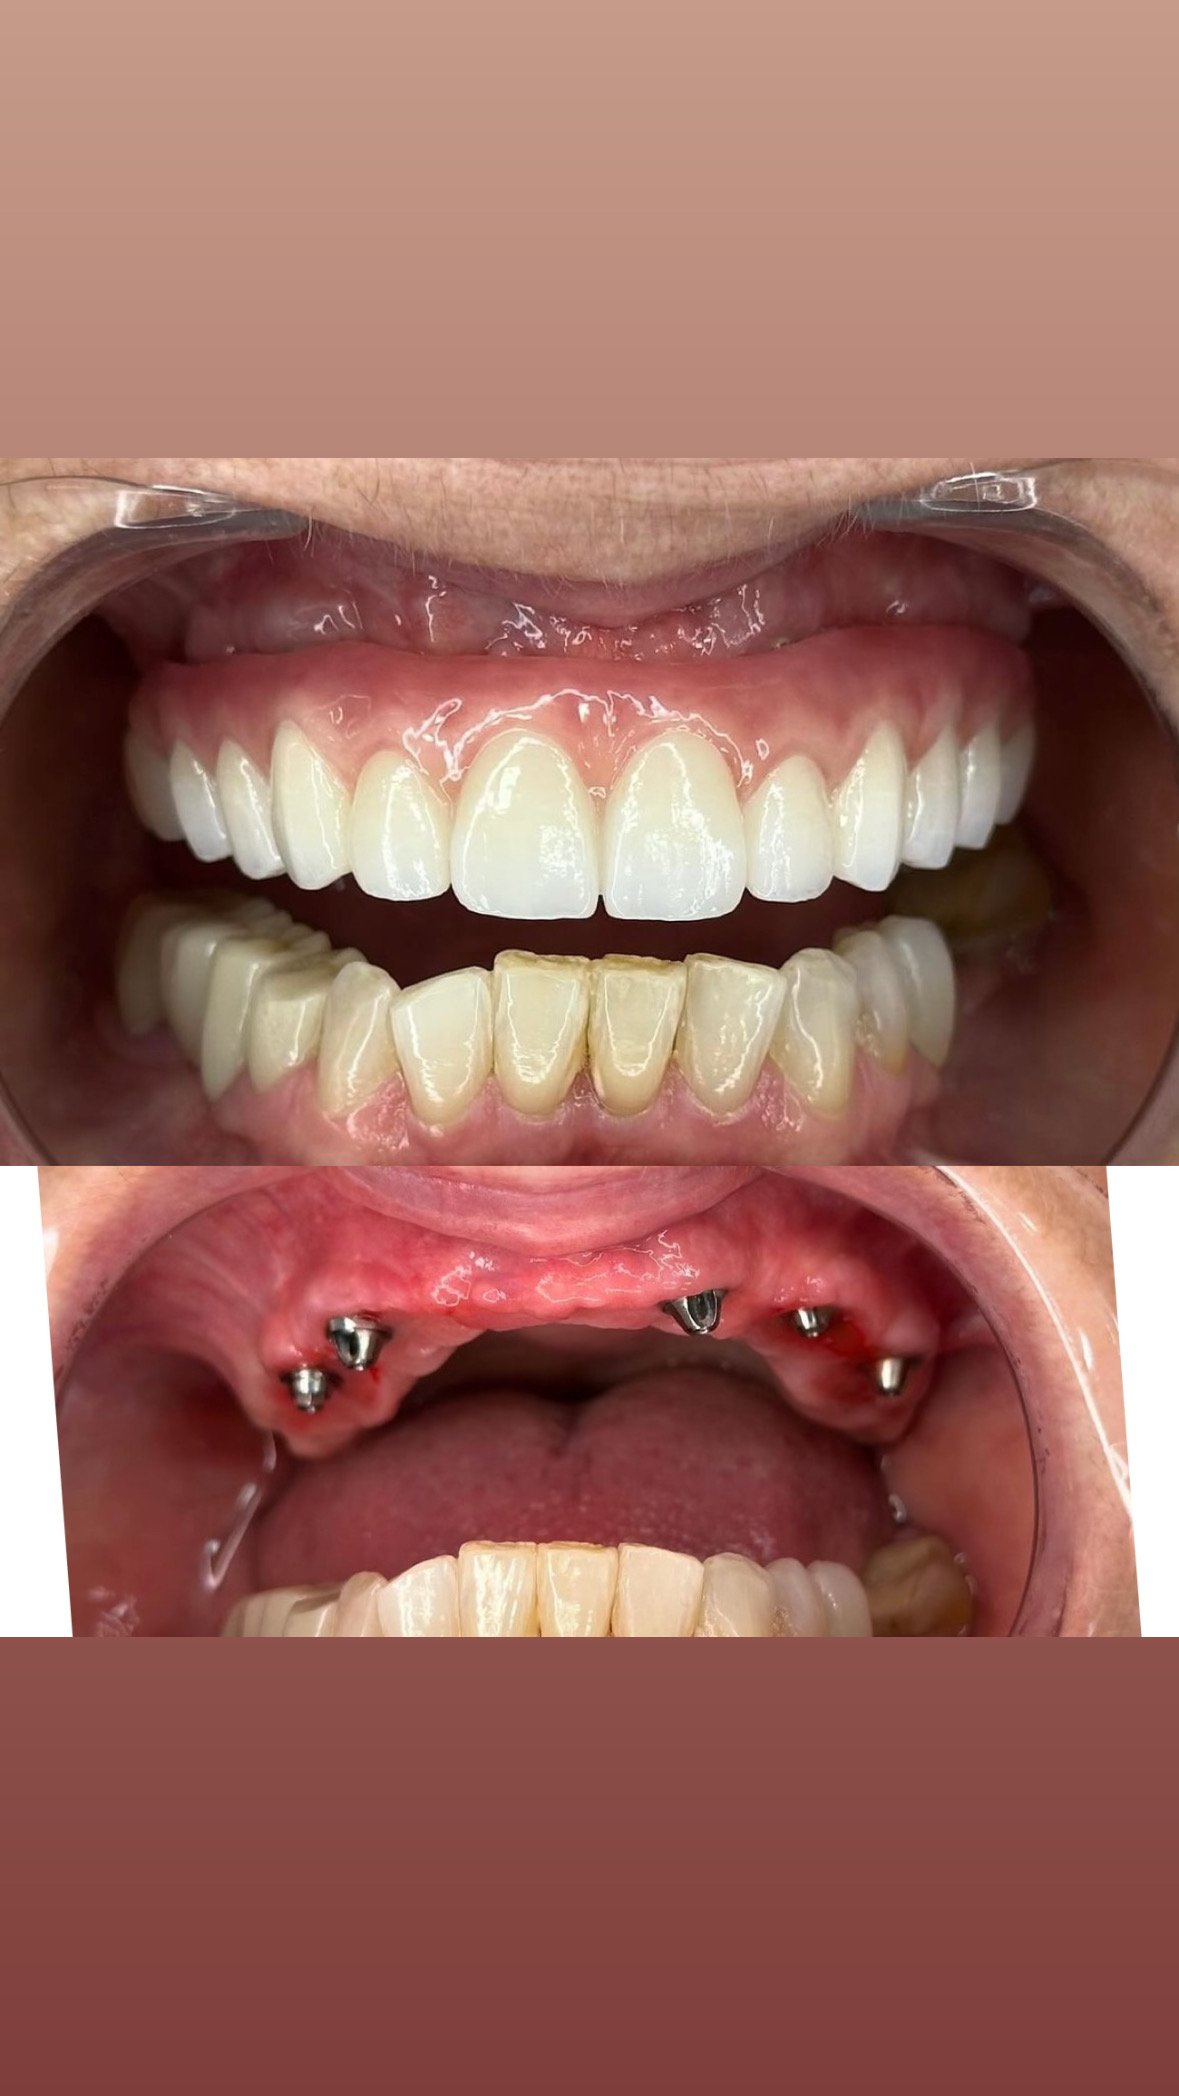

Screenshot